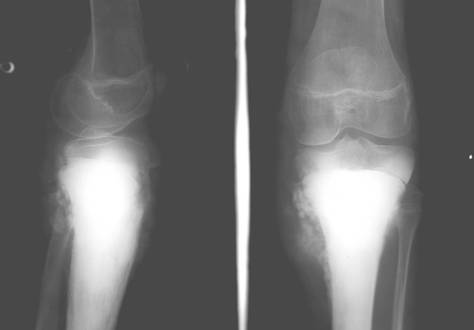

b)   Tumora cu mieloplaxe (celule gigante) – se intalneste exclusiv la adulti, afectand mai ales femeile. Are sediu epifizar, predilect langa genunchi si realizeaza o imagine transparenta, excentrica ce umfla osul. Imaginea descrisa are o structura neomogena data de travee opace ce dau un aspect de fagure tumorii. Corticala este impinsa in afara si subtiata. Trecerea intre tumora si diafiza sanatoasa are loc brusc, dand compactei un aspect amputat

Fig. 84 – Tumora cu mieloplaxe